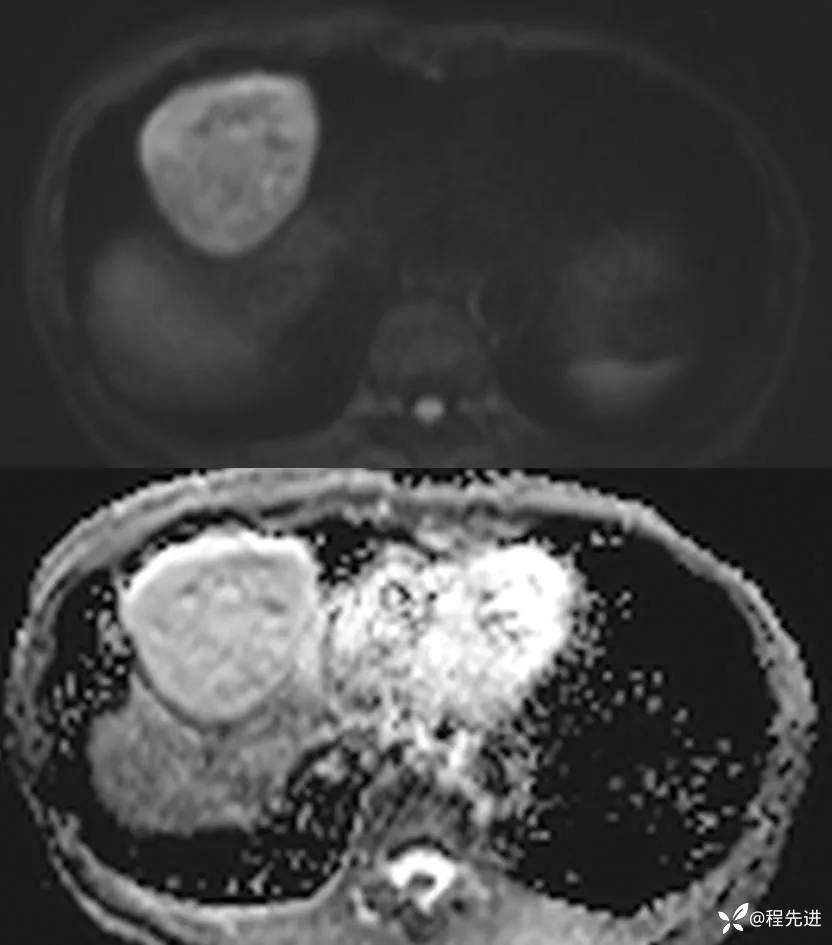

MRI平扫+增强: